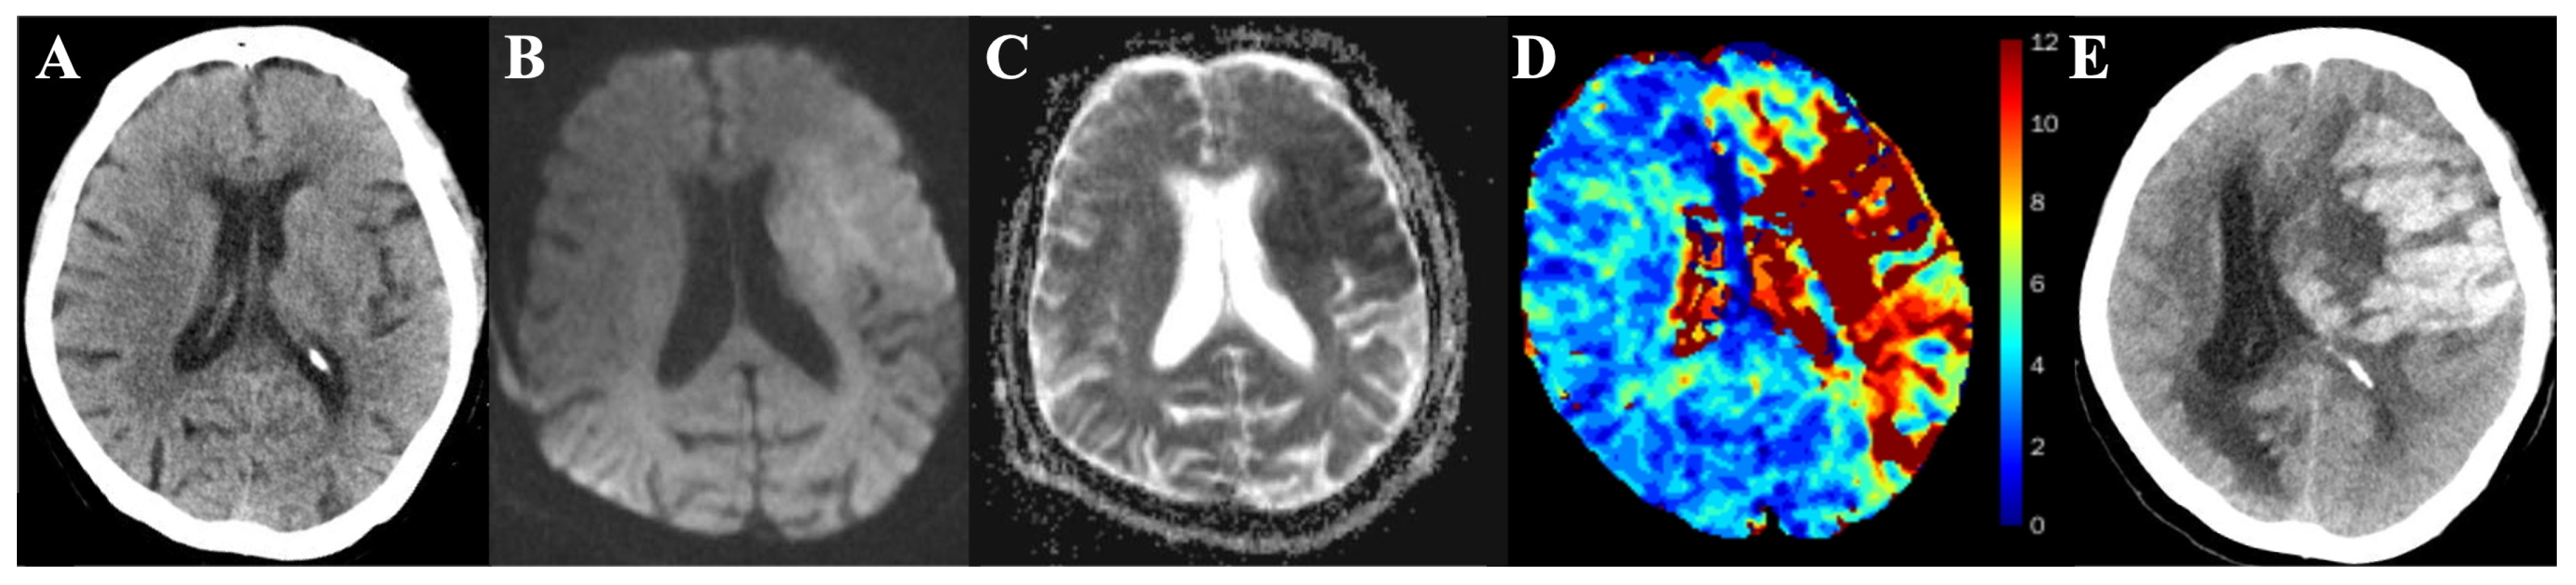

2.2. MR Protocol

2.3. Image Process